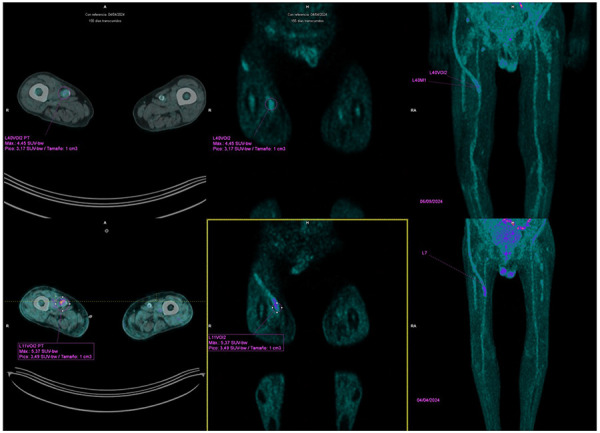

Successful rezafungin treatment of an azole-resistant <i>Candida parapsilosis</i> vascular graft infection.

Successful rezafungin treatment of an azole-resistant Candida parapsilosis vascular graft infection.